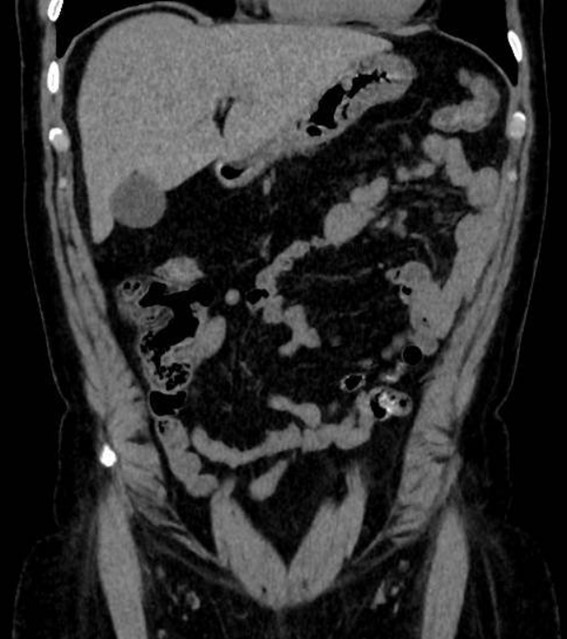

Ante la sospecha de cólico nefrítico complicado, se realiza ecografía abdominal, que muestra en fosa ilíaca izquierda, un foco ecogénico con sombra acústica posterior y engrosamiento de la pared intestinal de 6 mm. Se confirma mediante tomografía computarizada la presencia de divertículos en el colon izquierdo, con un divertículo engrosado entre el colon descendente y sigma, y discretos cambios inflamatorios pericólicos. Con mínimo líquido en la gotiera adyacente, sin colecciones ni burbujas de gas extraluminal.

Este caso subraya la importancia de una anamnesis completa y exploración física, que aunque no definitivas, ayudan a orientar el diagnóstico diferencial. Aunque diagnósticos comunes como el cólico nefrítico son frecuentes, es crucial no descartar otras patologías que podrían complicarse sin tratamiento adecuado. La ecografía, como herramienta inicial, permitió detectar signos de diverticulitis aguda no complicada, orientando el diagnóstico y tratamiento. Complementada por la tomografía computarizada, la ecografía demostró ser útil en el dolor abdominal localizado, destacando la importancia de un diagnóstico integral y el uso adecuado de herramientas disponibles.